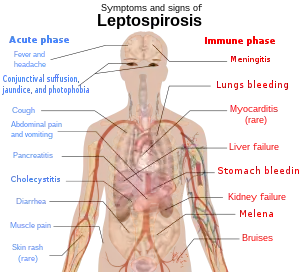

Signs and symptoms

The symptoms of leptospirosis usually appear one to two weeks after infection,[7] but the incubation period can be as long as a month.[20] The illness is biphasic in a majority of symptomatic cases. Symptoms of the first phase (acute or leptospiremic phase) last five to seven days. In the second phase (immune phase), the symptoms resolve as antibodies against the bacteria are produced.[8] Additional symptoms develop in the second phase.[21] The phases of illness may not be distinct, especially in patients with severe illness.[22] 90% of those infected experience mild symptoms while 10% experience severe leptospirosis.[23]

Leptospiral infection in humans causes a range of symptoms, though some infected persons may have none. The disease begins suddenly with fever accompanied by chills, intense headache, severe muscle aches and abdominal pain.[5][20] A headache brought on by leptospirosis causes throbbing pain and is characteristically located at the head's bilateral temporal or frontal regions. The person could also have pain behind the eyes and a sensitivity to light. Muscle pain usually involves the calf muscle and the lower back. The most characteristic feature of leptospirosis is the conjunctival suffusion (conjunctivitis without exudate) which is rarely found in other febrile illnesses. Other characteristic findings on the eye include subconjunctival bleeding and jaundice. A rash is rarely found in leptospirosis. When one is found alternative diagnoses such as dengue fever and chikungunya fever should be considered. Dry cough is observed in 20–57% of people with leptospirosis. Thus, this clinical feature can mislead a doctor to diagnose the disease as a respiratory illness. Additionally, gastrointestinal symptoms such as nausea, vomiting, abdominal pain, and diarrhoea frequently occur. Vomiting and diarrhea may contribute to dehydration. The abdominal pain can be due to acalculous cholecystitis or inflammation of the pancreas.[20] Rarely, the lymph nodes, liver, and spleen may be enlarged and palpable.[8]

There will be a resolution of symptoms for one to three days.[7] The immune phase starts after this and can last from four to 30 days and can be anything from brain to kidney complications.[24] The hallmark of the second phase is inflammation of the membranes covering the brain.[7] Signs and symptoms of meningitis include severe headache and neck stiffness.[7] Kidney involvement is associated with reduced or absent urine output.[7]

The classic form of severe leptospirosis, known as Weil's disease, is characterised by liver damage (causing jaundice), kidney failure, and bleeding, which happens in 5–10% of those infected.[7] Lung and brain damage can also occur. For those with signs of inflammation of membranes covering the brain and the brain itself, altered level of consciousness can happen. A variety of neurological problems such as paralysis of half of the body, complete inflammation of a whole horizontal section of spinal cord, and muscle weakness due to immune damage of the nerves supplying the muscles are the complications. Signs of bleeding such as non-traumatic bruises at 1 mm (0.039 in), non-traumatic bruises more than 1 cm (0.39 in), nose bleeding, blackish stools due to bleeding in the stomach, vomiting blood and bleeding from the lungs can also be found. Prolongation of prothrombin time in coagulation testing is associated with severe bleeding manifestation. However, low platelet count is not associated with severe bleeding.[20] Pulmonary haemorrhage is alveolar haemorrhage (bleeding into the alveoli of the lungs) leading to massive coughing up of blood, and causing acute respiratory distress syndrome, where the risk of death is more than 50%.[20] Rarely, inflammation of the heart muscles, inflammation of membranes covering the heart, abnormalities in the heart's natural pacemaker and abnormal heart rhythms may occur.[8]